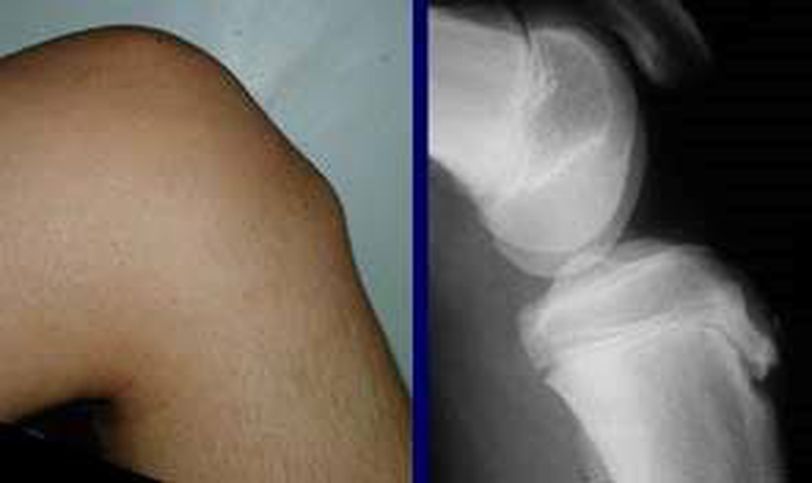

A disease primarily affecting young athletic boys, Osgood-Schlatter disease is a traction injury of the immature tibial apophysis. This results in the inflammation of the tibial tuberosity at the insertion of the patellar tendon. The Xray lateral view of the knee shows an ossification separated from the main tibia. On gross inspection, a bump may be seen over the upper tibia. Image via: https://www.ortho.wustl.edu/content/Patient-Care/3188/Services/Pediatric-and-Adolescent-Orthopedic-Surgery/Overview/Knee-Education-Overview/Osgood-Schaltters.aspx